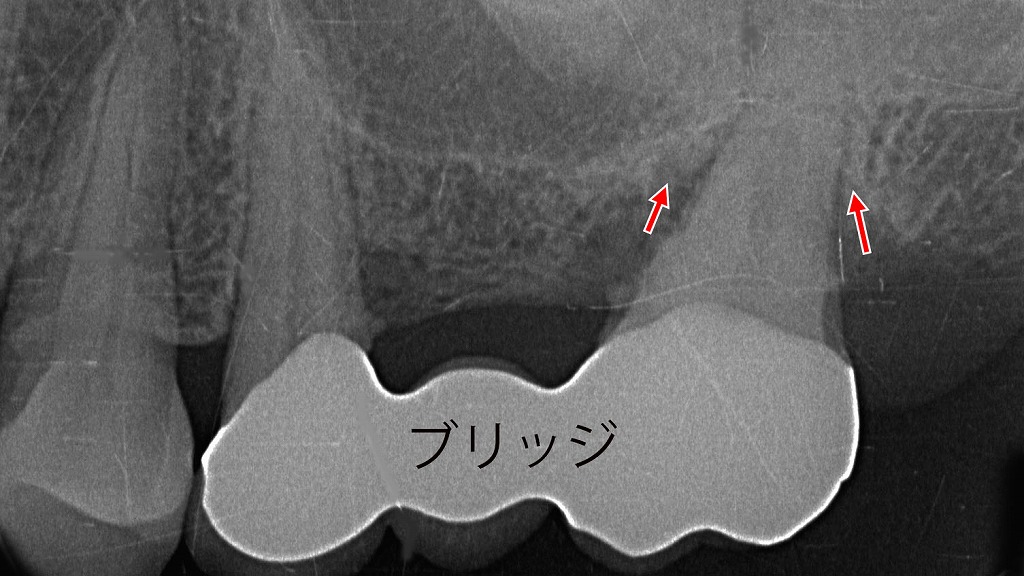

6番欠損に対する5・6・7番ブリッジ|7番の重度歯周病による歯槽骨吸収で抜歯に至った症例

上顎6番欠損に対して、5・6・7番を支台としたブリッジ治療が行われていた症例です。

レントゲン像では、7番周囲の歯槽骨が著しく吸収しており(矢印部)、重度歯周病による支持骨の喪失が認められます。ブリッジの支台歯として長期間負担が集中したことも一因となり、保存は困難と判断し7番は抜歯に至りました。

欠損補綴では、支台歯の歯周状態を含めた長期的な予後評価が重要であることを示す症例です。